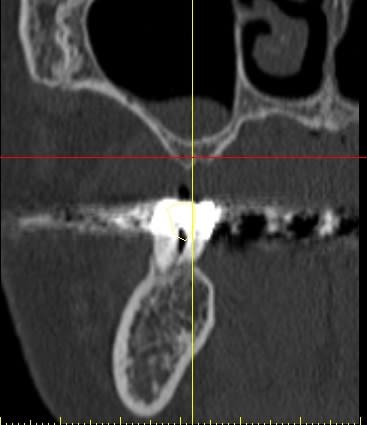

pour votre plaisir mon ami 8 mois d'écarts

fenêtre fermée par du vitalos pas de membrane technique "grosse ouverture"

ce qui ne me plait pas dans ton cas pxav c'est que tu n'as pas décollé la paroi médiale du sinus, tu fais une grosse fenêtre du coup tu te prives d'un apport vasculaire non négligeable.

la demande était radio à J et J+6 mois, pas "présentez un cas de comblement de sinus parfait".

Perso je trouve le résultat "correct" imagine si en plus j'avais fais un CS nickel...